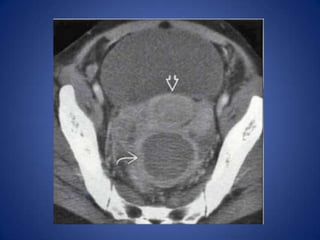

• Uterine Fibroids

– May torse , undergo degeneration or infarction,

lead to acute pain

– Heterogeneous soft tissue masses within enlarged

uterus, ± focal calcifications within masses

Gynecologic Causes • Many,including adnexal infection & masses, torsed ovary, endometriosis, etc. • Look for evidence of mass &/or inflammation centered on adnexa, rather than bowel • Uterine Fibroids – May torse , undergo degeneration or infarction, lead to acute pain – Heterogeneous soft tissue masses within enlarged uterus, ± focal calcifications within masses